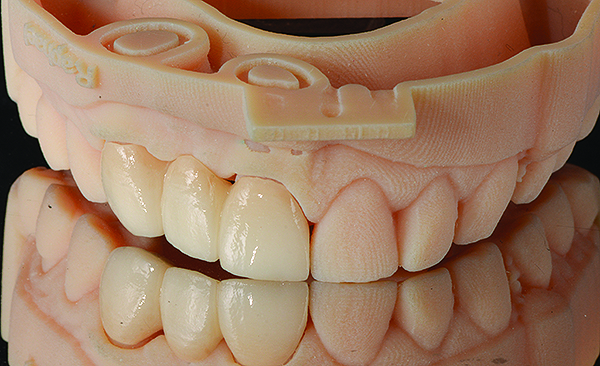

(7.) Completed restoration seated on a model reproduced from the optical impression.

Figure 7

Based on the virtual plan, the treatment is carried out. An example of virtually planned and executed treatment is shown in Figure 2 through Figure 7. The patient presented with a missing maxillary right lateral incisor (Figure 2). Based on the patient’s desires, expectations, and comprehensive examination, a lithium disilicate fixed dental prosthesis (FDP) was planned to restore the missing lateral incisor. A virtual mock-up of the desired treatment plan was performed to delineate tooth length, width, and emergence profile (Figure 3). The treatment plan was then executed by preparing the abutment teeth to receive the FDP (Figure 4). An optical impression was made of the preparations and opposing teeth, and the resulting scans were virtually articulated (Figure 5). The optical impression was used to evaluate all aspects of the preparation, including finish line width and finish, path of insertion, and occlusal and axial reduction. It was also examined for the presence of undercuts, which were delineated by a red color (Figure 6). Errors in preparation design can be easily corrected and a new optical impression of the modified areas can be made without having the patient return for another visit. Once completed, the digital files can be sent to the laboratory for restoration design and manufacture, or used to design and fabricate the restoration using an in-house milling machine.14 An example of a completed restoration is shown in Figure 7.